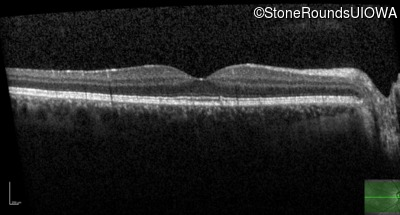

Optical Coherence Tomography - Left - 20/16 -2

Exemplar / OCT Stack